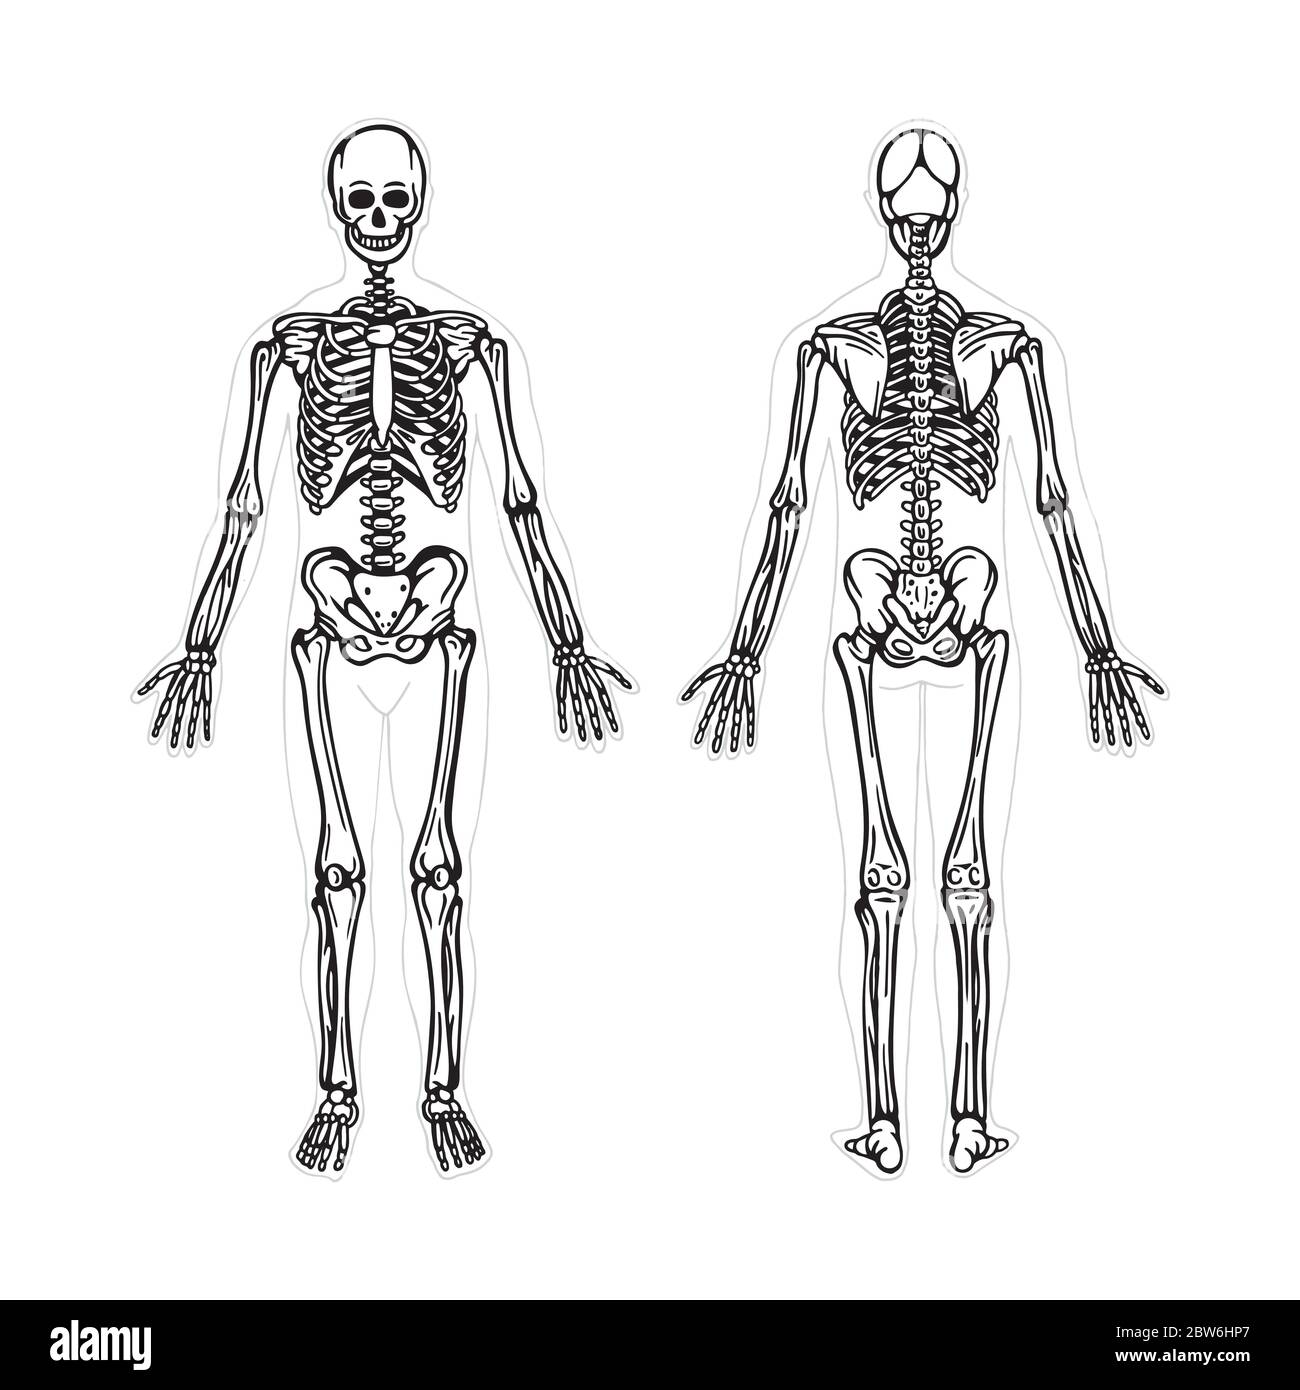

RF2BW6HP7–Squelette. Squelette humain dessin à la main illustration vectorielle. Squelette humain, vue avant et arrière. Système osseux. Partie de l'ensemble.